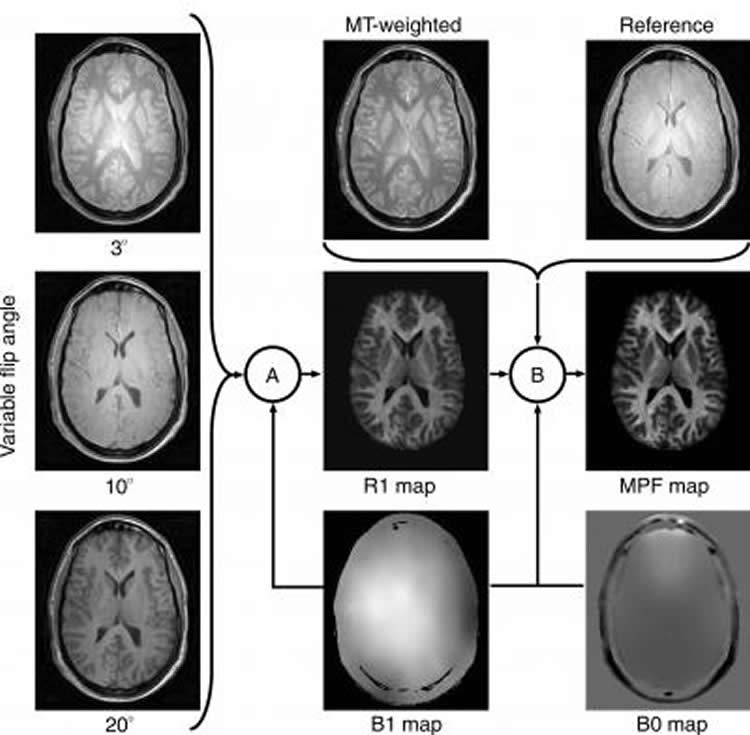

The scheme demonstrating how an MPF map is computed from source MR images. Imaging protocol includes three gradient-echo images with variable flip angles, a gradient-echo image with off-resonance radiofrequency saturation enabling the magnetization transfer effect (MT-weighted image), and a reference image that is a similar gradient-echo image obtained without saturation. Additionally, an MR imager produces maps of the main magnetic field (B0) and radiofrequency field (B1), which are used to correct errors caused by imperfectness of imager’s hardware. MPF maps are computed voxel-by-voxel in two steps, (A) and (B), using special software developed by the authors. During the first step (A), a map of the longitudinal relaxation rate (R1) is generated as described in the literature. This map along with an MT-weighted image and a reference image are used to compute an MPF map in the second step (B) based on an iterative algorithm recently described by the authors. Credit Radiological Society of North America.